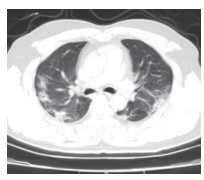

2.5 胸部CT结果入院时,为所有患者进行了胸部螺旋CT检查,47例(71.2%)患者表现为双侧多发性斑片样和磨玻璃样混浊,典型影像学表现见图 1,19例(28.8%)患者表现为单侧肺炎,典型影像学表现见图 2。

| 图 1 双肺感染 Fig 1 Bilateral lung infection |

在入院治疗3 d后,再次对所有患者复查了胸部螺旋CT。39例(59.1%)患者肺部感染灶有不同程度增多,27例(40.9%)患者肺部感染灶无明显进展。